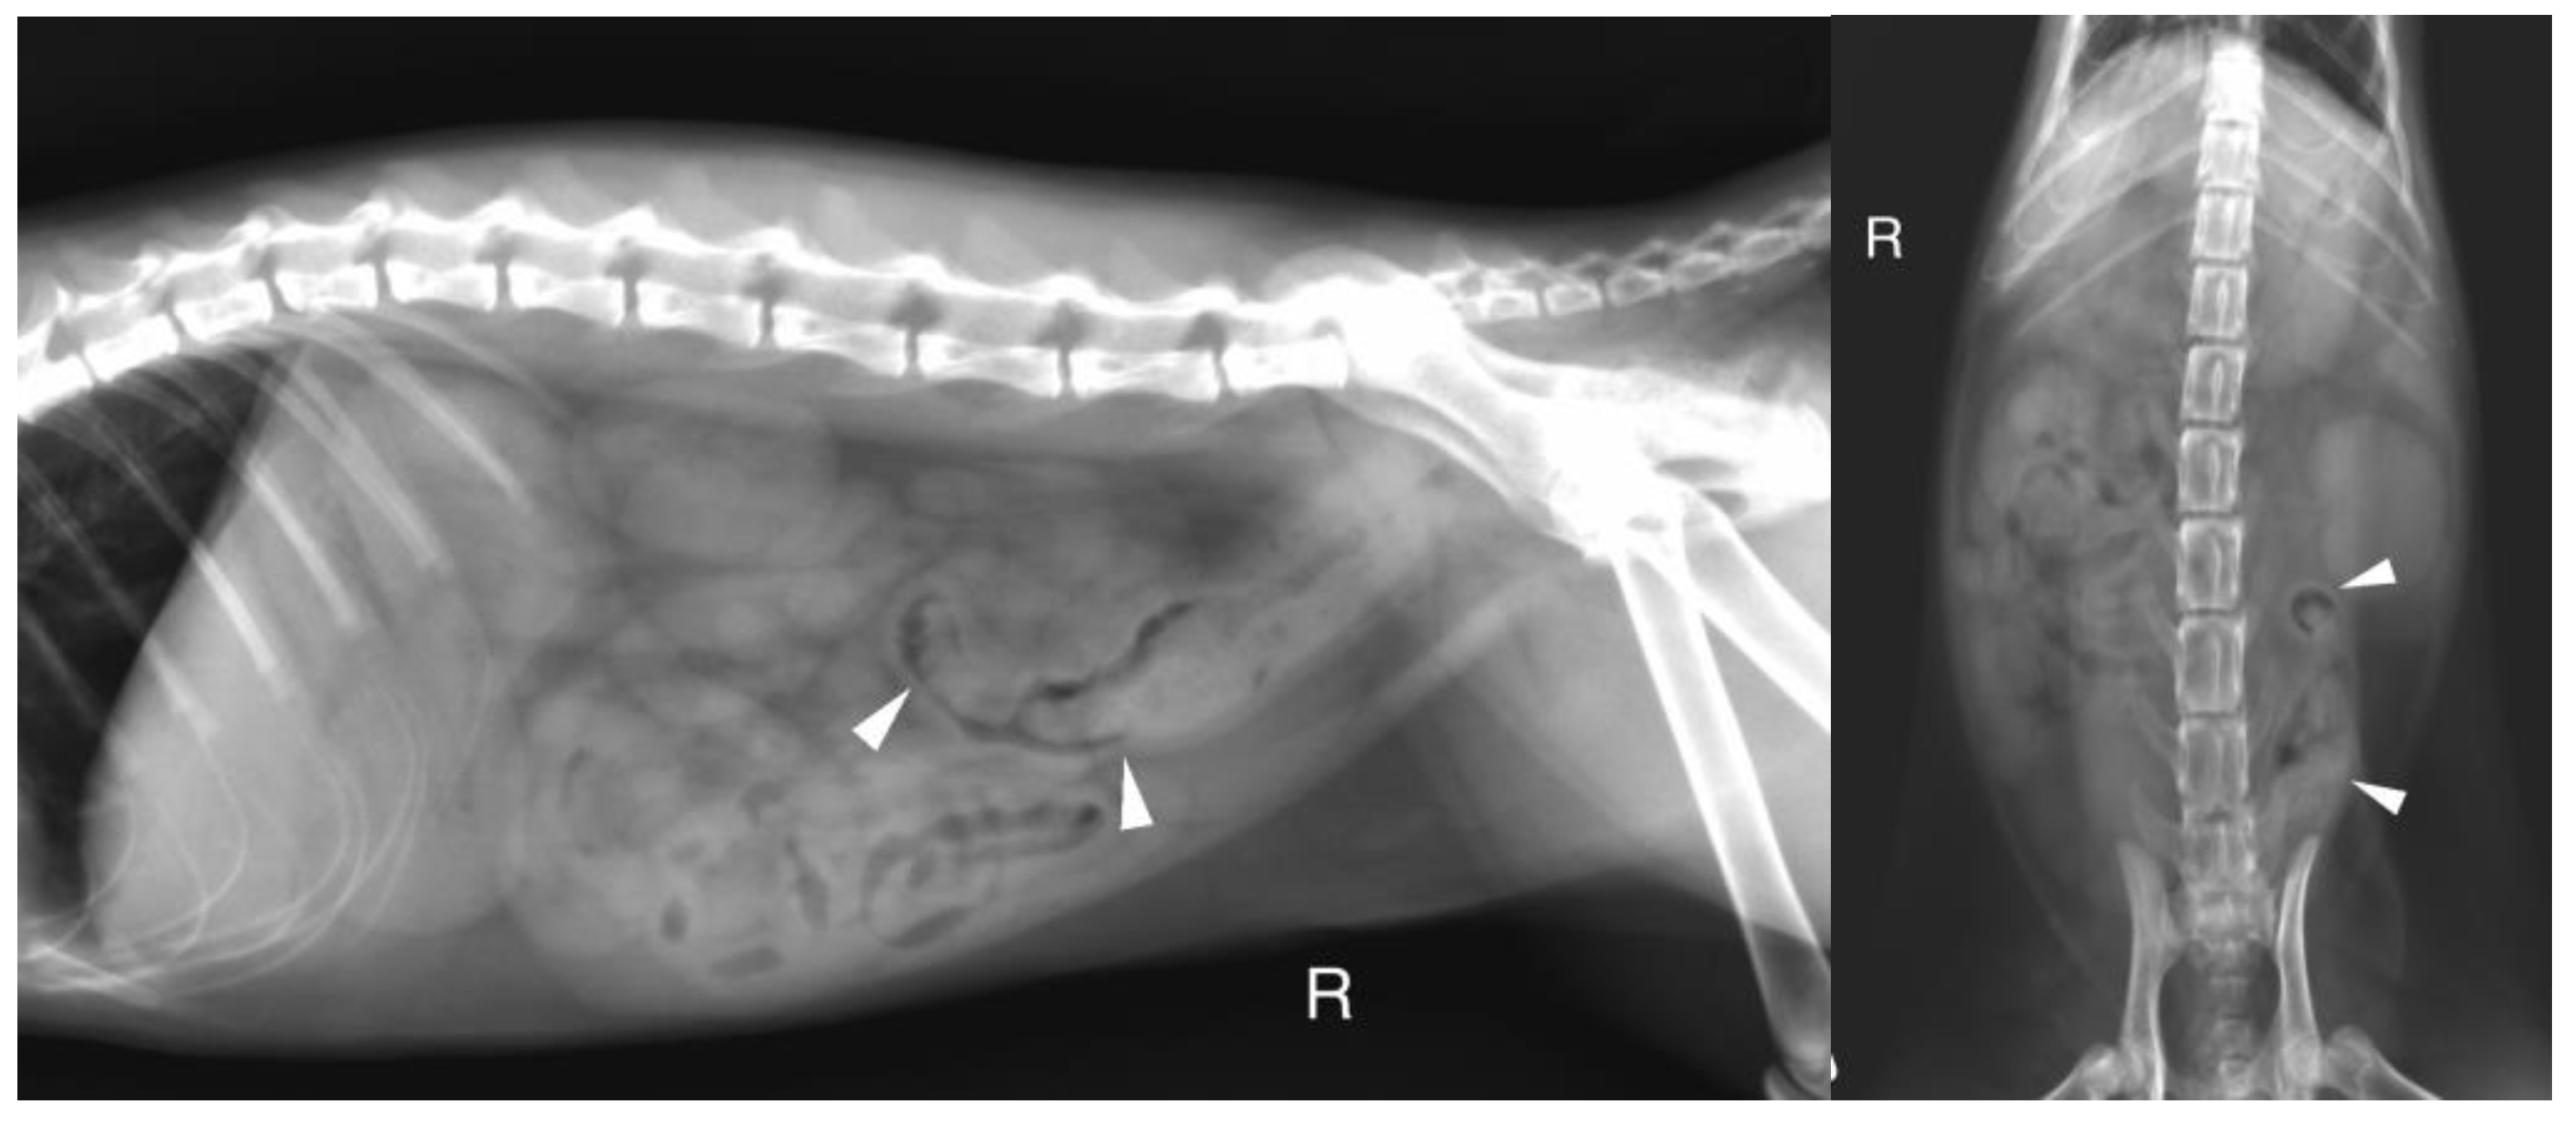

Abdominal radiographs were acquired in 5 cases (4 cats and one dog). In two cats, the descending colon showed an abrupt ending with a total length approximately half as long as expected. No ascending nor transverse colon could be identified in these 2 cases (Figure 2). In the dog, the cecum appeared mispositioned in the left cranial abdominal quadrant and seemed associated with a focal area of colonic lumen narrowing 22 cm orally to the anus (Figure 3). Positive contrast colonography were performed in 3 cases (three cats) and allowed the diagnosis of partial colonic agenesis in all of them (Figure 4).

Figure 3. A. Right lateral radiograph and B. Ventro-dorsal radiograph of the abdomen of case 18, an 8 years-old Colley dog. The cecum is malpositioned in the left cranial and dorsal abdomen (white arrow heads), in continuity with the descending colon on the lateral view (black arrows). A focal narrowing of the aboral part of the descending colon is observed before it enters the pelvis (black arrow heads).